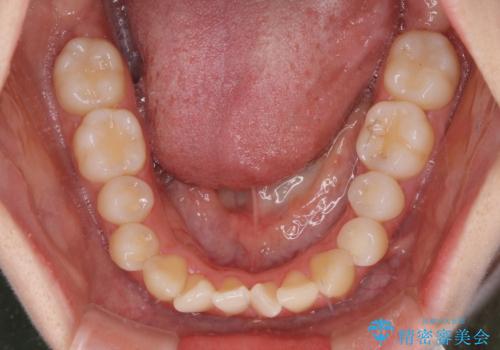

- 前歯のデコボコと非接触の上下前歯を気にして来院された患者様です。

上下前歯の隙間は舌の突出癖によるもので、隙間改善のためには舌のトレーニングがとても重要となります。

治療開始当初は舌の突出癖が改善されておらず、上下前歯の隙間がより顕著な状態となりました。

舌のトレーニングは、突出癖がなくなるまで必要であり、矯正治療後に突出癖が残ると、あっという間に隙間が空き、後戻りでデコボコとなってしまいます。